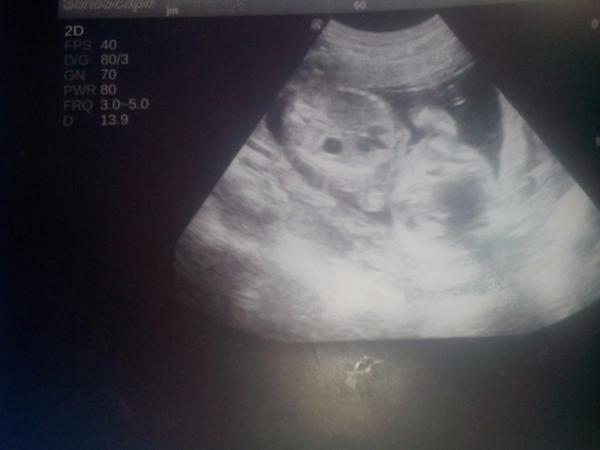

@prostejina tak zatim nic nevime dr. nema tk dobrej ultrazvuk jak na genetice (aspon to je muj dojem pže prcek nešel vidět tk dobře jak v utery) a nedokaže nam nic řict až prej okolo 16-20t 🙂 tak si ještě chvilku počkame.)

@tonaeva Jé teď se dívám pořádně a pardon - z toho nevykoukám vůbec nic! nožičkama je jakoby z boku...